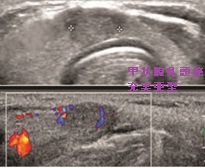

- 甲状腺超音波(エコー)検査において、不均一な病変で

等エコー(48.4%)、びまん性粒状石灰化(52.3%)、血流は乏しい(71.6%)

- 甲状腺エコーで、境界不明瞭で不均質な病変;等エコー(48.4%)、びまん性粒状石灰化(52.3%)、血流は乏しい(71.6%)[Clin Radiol. 2022 May;77(5):e356-e362.]

(エコー画像;Ultrasonography. 2017 Apr 36(2) 103–110.)